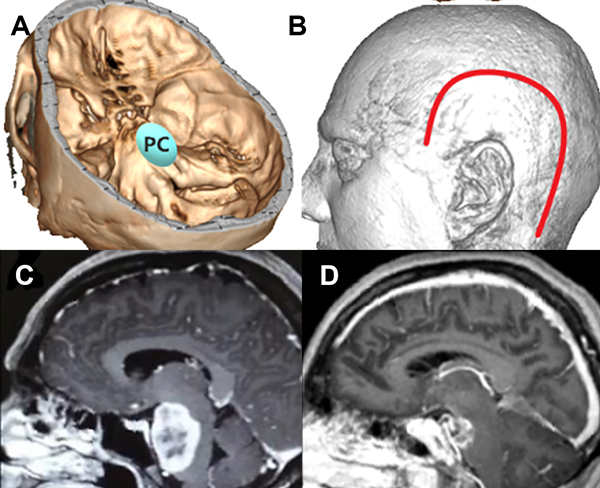

Figura 5: Paciente con meningioma de base de cráneo petroclival (PC) (2 puntos), en su diámetro máximo midió 5 cm (2 puntos) sin invasión ósea, total: 5 puntos, baja probabilidad de resección total. A: localización de lesión en base de cráneo. B: abordaje realizado combinado. C: resonancia con contraste corte sagital prequirúrgica. D: resonancia con contraste corte sagital posquirúrgica con resección subtotal de lesión.